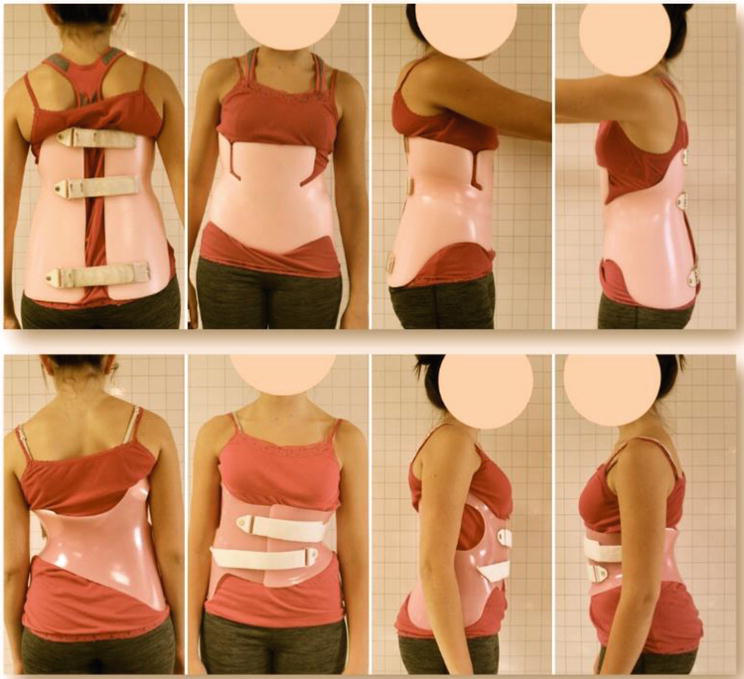

Bracing

While it has recently been determined that wearing a back brack won’t correct or reverse scoliosis progression, it can help the spinal curvature from worsening in children. The most common type of brace called a Wilmington or Boston brace depending on how it fastens, is made of hard plastic on the outside, with contouring foam on the inside to hold an s-shaped spine in a mostly-straight position day and night. For c-shaped curves, a Charleston brace is used to overcorrect the lower spine and prevent forward progression at night.

Activity while wearing a back brace does not usually need to be restricted, and the brace can be removed to shower or do more rigorous activities. The more hours a brace is worn, the more effective it becomes in stopping forward progression. In some cases, consistent bracing is enough to prevent surgery.